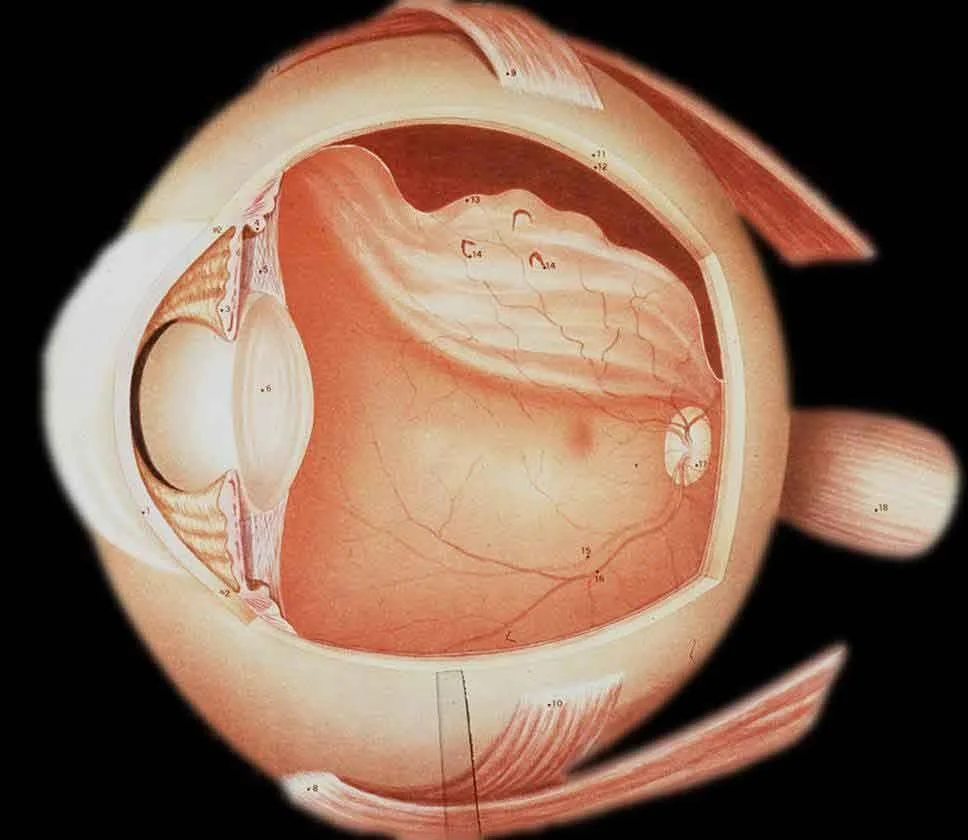

-

Retinal detachment denotes separation of the sensory retina from the underlying RPE

There are three main types:

- Rhegmatogenous

- Traction

- Exudative